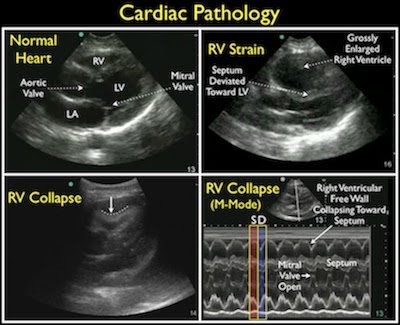

- Component: Heart (parasternal long axis view)

- Finding: Pericardial effusion (tamponade)

- Small effusions are best identified posterior to left ventricle (dependent portion of pericardium)

- Can find compression of the right ventricle (Singh S et al Sens 92%, Spec 100%, PPV 100%)

- Finding: Left ventricular ejection fraction estimation

- Look at anterior leaflet of mitral valve, which should normally touch septum

- <30% difference of LV size between systole and diastole indicates severely decreased LV function

- Finding: Right ventricular strain

- Normally RV should be 60% of LV size (If RV = LV size, this is abnormal)

- Lodato JC et al: If McConnell Sign (reduction in RV free wall motility with sparing of the apex) is present, specificity for PE is 96%, but sensitivity is 16%.

- Component: Heart (Subxiphoid)

- Probe: Phased array probe (3.5 – 5 MHz)

- Location: Subxiphoid, point toward left scapula